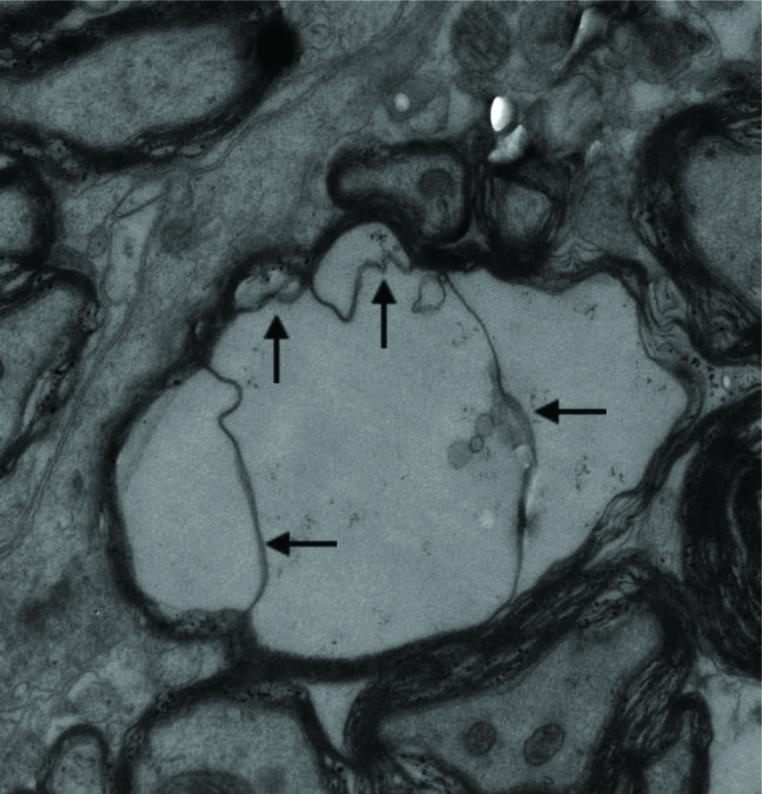

MATERIAL AND METHODS

BALB/c mice were challenged with prion RML strain and from 90 days post-challenge (dpc) mice were sacrificed weekly until all of them had been at 160 dpc. The ultra-structure and pathological changes of the brain of experimental mice were observed and recorded by transmission electron microscopy.

RESULTS

There were a large number of pathogen-like particles aggregated in the myelin sheath of the brain nerves, followed by delamination, hyperplasia, swelling, disintegration, phagocytic vacuolation, and other pathological lesions in the myelin sheath. The aggregated particles did not overflow from the myelin in unstained samples. The phenomenon of particle aggregation persisted all through the disease course, and was the earliest observed pathological change.

CONCLUSION

It was deduced that the myelin sheath and lipid rafts in brain nerves, including axons and dendrites, were the main sites for the conversion of PrP to PrP, and the PrP should be formed directly by the conversion of protein conformation without the involvement of nucleic acids.